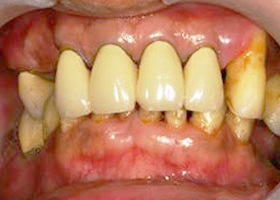

2. 治療前,口內照片。

proimages/case/Artificial_implant/all-2.jpg